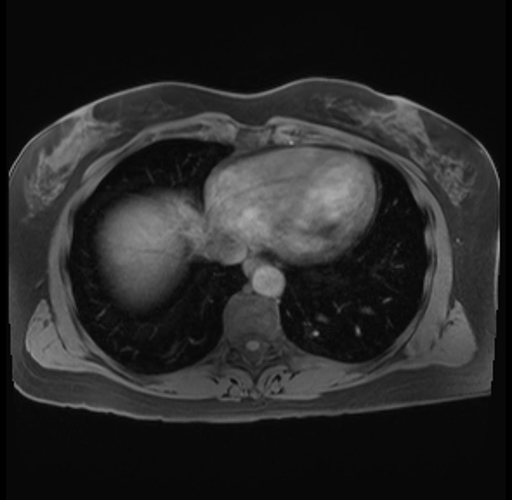

Imaging Analysis

Look through the patient's CT scan to identify any areas of concern for the necessary procedure.

Based on your CT findings, which issue(s) are present and would give reason for "planned slowing down moment(s)" in this case?

Considering a standard distal pancreatectomy procedure, what step(s) of the operation would you do differently in this case?